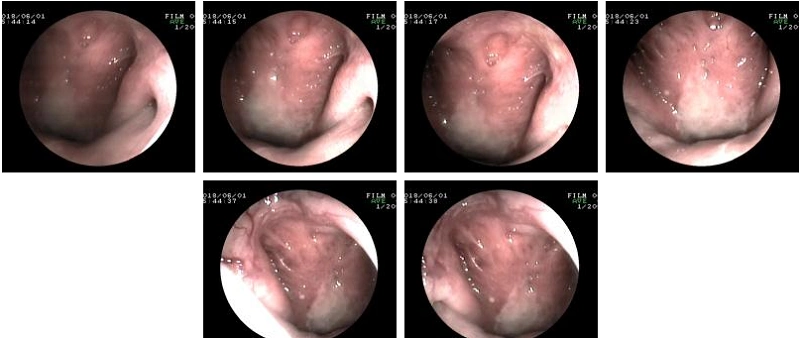

湘雅 湘雅医院 中南大学 间接鼻咽镜检查 正常鼻咽镜像 鼻咽癌镜像

这是我做的鼻咽镜检查,我会是鼻咽癌吗?

窄带成像内镜:鼻咽喉部肿瘤诊断的"照妖镜" - 好大夫在线